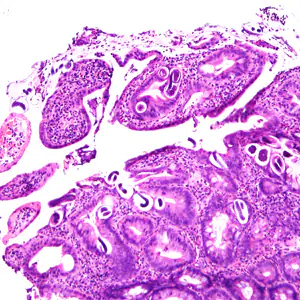

A 25-year-old male was hospitalized for Crohn’s exacerbation, duodenal outlet obstruction, and regional enteritis. He indicated that he has not had recent travel abroad. The patient underwent a gastroenterostomy and duodenal biopsy specimens revealed acute and chronic inflammation with crypt abscesses, focal ulceration, and reactive epithelial changes. Granulomata, epithelial dysplasia, and fibrosis were lacking. The attending pathologist also noted suspect parasitic organisms and the slides were sent to the state health department, which in turn forwarded them to the CDC-DPDx for diagnostic assistance. Figures A–F show what was observed on the slides received for testing. Figure A was taken at 100x magnification; Figures B–D at 400x magnification; and Figures E and F at 1000x magnification with oil. What is your diagnosis? Based on what criteria?

Figure A